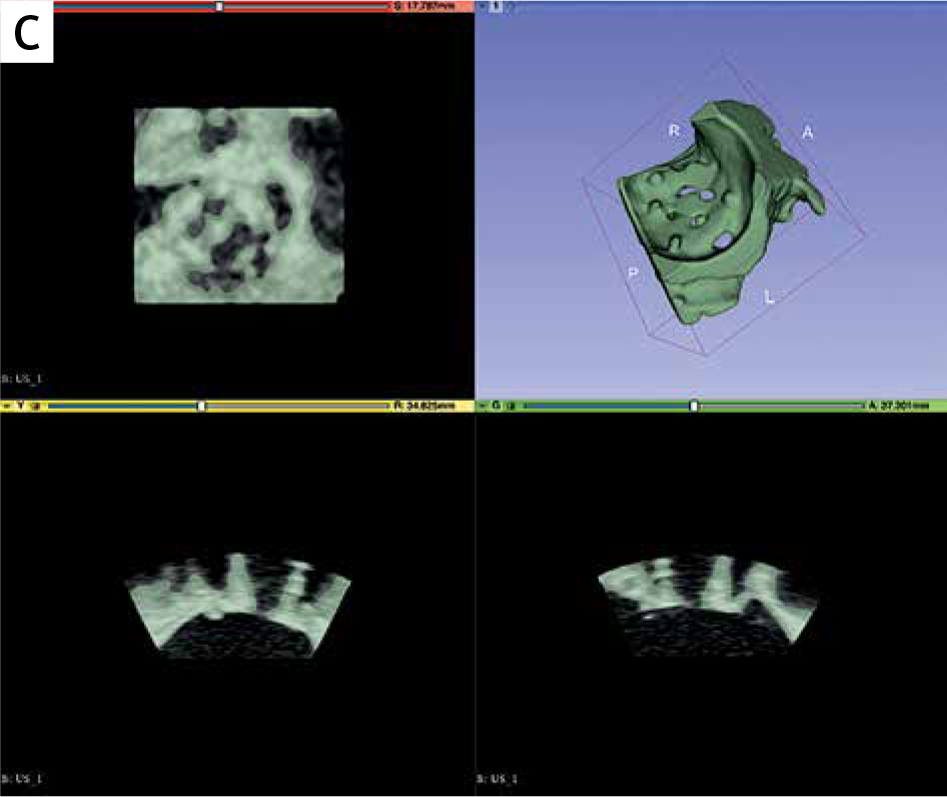

Zespół z GCM i ŚUM wykorzystał dane z echokardiografii 3D-TEE, które po konwersji do plików 3D, dzięki segmentacji w oprogramowaniu powiązanym z drukarką 3D (slicer), zostały wydrukowane w rzeczywistej skali na drukarce Stratasys Objet 30 (v.3) w technologii PolyJet.

Do druku modeli użyto materiałów sztywnych (IORA Model i IORA Support dla koniecznych w pracy drukarki podpór, oba firmy Isquared). Na drukarce Objet 30 uzyskać można wysoką dokładność odwzorowania struktur anatomicznych z odchyleniem nieprzekraczającym ±100 μm przy modelach poniżej 100 mm długości.

W projekcie przeanalizowano 8 przypadków pacjentów z PVL w mitralnych zastawkach mechanicznych lub biologicznych. W testach symulacyjnych przeprowadzonych na wydrukowanych modelach, dobrano optymalne rozmiary okluderów, co później porównano z rzeczywistym postępowaniem klinicznym.

Parametry druku modeli i procedury:

- Średni czas przygotowania danych: 90–130 minut

- Średni czas druku: 280–800 minut

- Modele drukowano w skali 1:1

- Wydrukowano z materiału sztywnego, przezroczystego

- Segmentacja obejmowała wybór ramek rozkurczowych dla lepszej widoczności kanału PVL

- Przykładowe rozmiary okluderów: PLD-W – 12×5 mm, AVP III – 10×5 mm, 8×4 mm